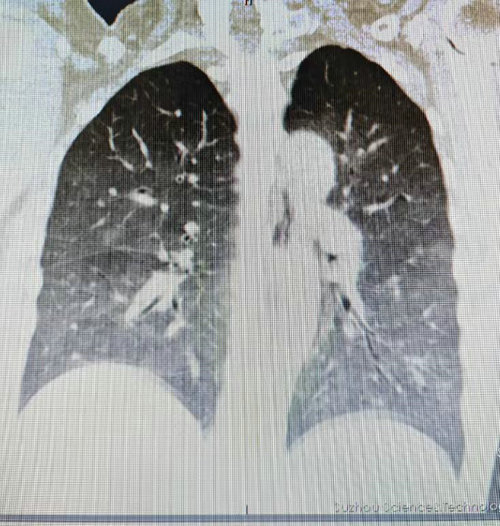

女子反复高热拖成“白...